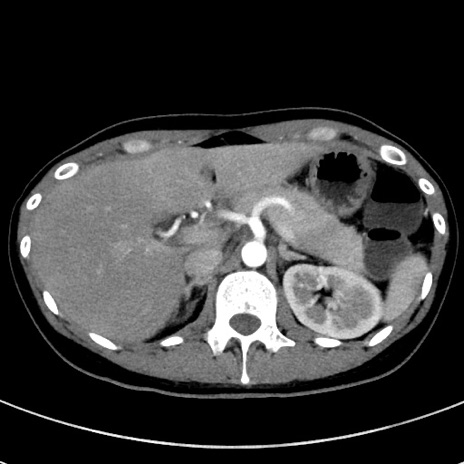

症例17(横断像)

【症例】20歳代女性

【主訴】嘔吐、下腹部痛

【現病歴】昨日夕食後に嘔吐し下腹部痛が出現。本日になっても嘔吐持続し改善しないため来院。

【身体所見】意識清明、BT 37.2℃、BP 108/67mmHg、腹部:平坦、やや硬、下腹部正中から右にかけて圧痛あり、反跳痛軽度あり、tapping pain(+)。

【データ】WBC 13600、CRP 14.94